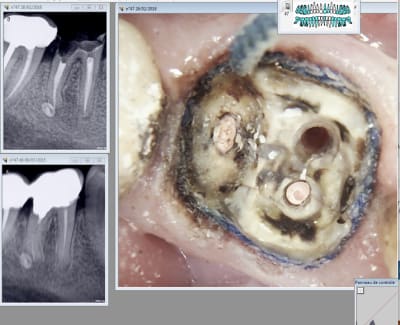

chicot29

26/02/2018 à 20h57

le vieux con a investi. -))))

Empreinte scan post en place.

L'autre est pas Top. Trop pressé de faire l'empreinte et toute mon attention a été captée pour trouver les limites en distal. 4 mm sous gingival. Après un . RTE sportif + dépose couronne soudée ( j'ai re scellé la 47)

Là tu te dis ca va saigner ! -))) Donc tu recrées un sillon gingival au laser + double fil.

Première empreinte......

Tiens ? Un micro trou dans le composite du moignon. Je l'avais pas vu meme avec des loupes. -))))